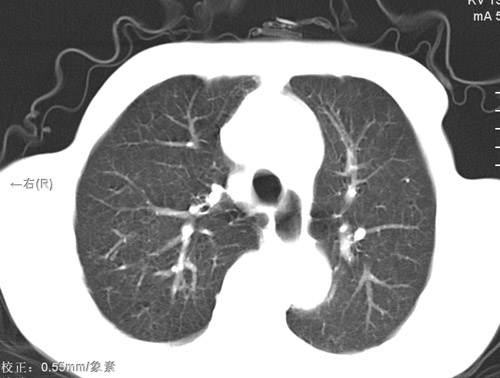

标题: CT17529:男 76 胸背部不适半月 胸透支气管炎 行CT检查 [打印本页]

标题: CT17529:男 76 胸背部不适半月 胸透支气管炎 行CT检查

意见 老年肺 少许炎症 肺大泡 右肺门略大 但支气管通畅  请各位高手指教如何下意见

间质纤维化伴少许炎症!另:肺大泡形成!

支持楼主意见,右肺门略大,可能为肺动脉增粗.

慢支肺气肿,肺动脉高压.